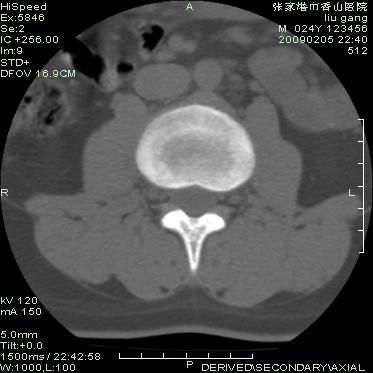

以下是引用随光逐影在2009-3-11 14:43:00的发言:[br]平片:l3、4、5及s1前上缘见类似“切角征”。[br]ct扫描:腰椎多个节段椎间盘向椎体内(椎体前部)突出。